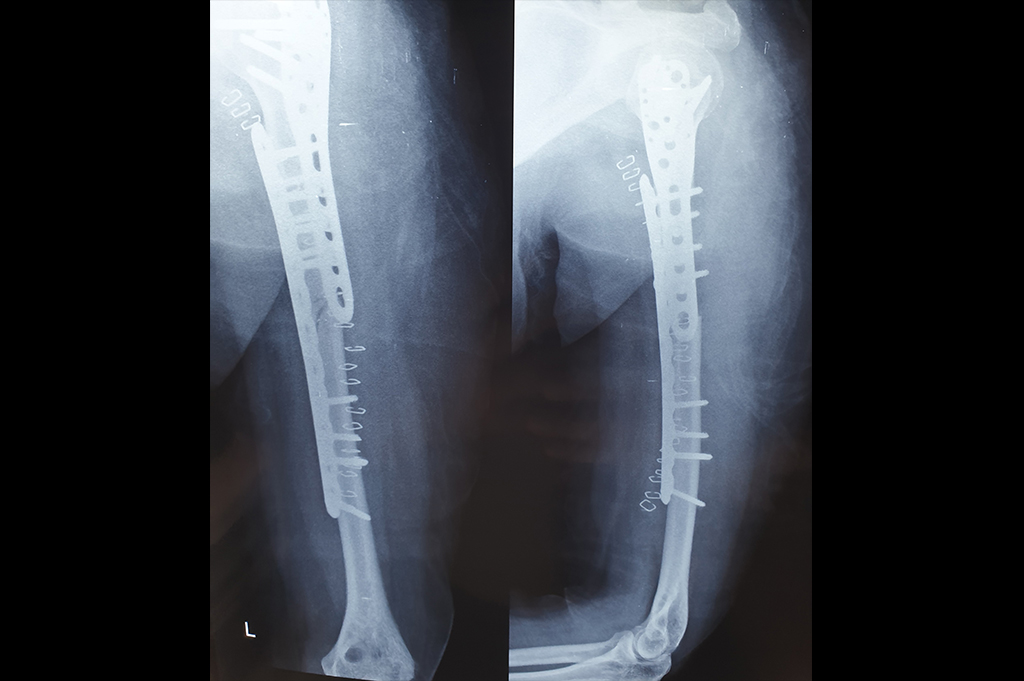

Humerus

Proximal Humerus

Subtrochanteric Fracture